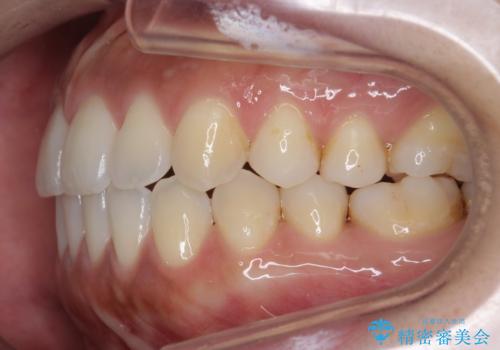

受け口、すきっ歯を インビザラインで モニター治療

- 前歯のすき間と受け口を気にして来院。

マウスピースでしっかり閉じています。

下の前歯を後方に移動するため、ゴムを上下のマウスピースにかけてもらいました。